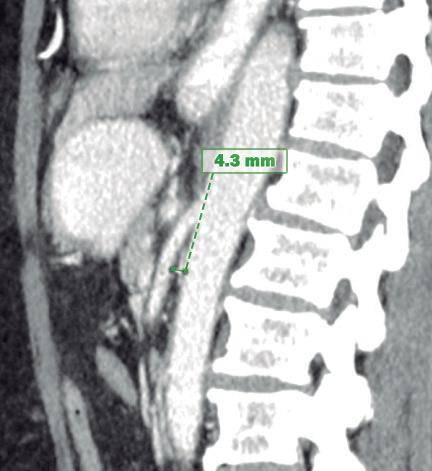

Paciente con vómitos en el periodo posoperatorio

Germán Francisco Rojas, Gabriel Adrián Mariño Camacho, Jesica Antonella Andruetto, Martín José Drago, Alejandro Moreira Grecco, Mariano Volpacchio, Esteban González Ballerga

Patient with Postoperative Vomiting